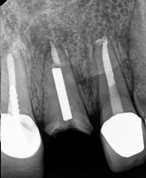

Conventional Endodontic Treatment with Post and Core Coronal Restoration

Conventional Endodontic Treatment/Retreatment with Prefabricated Bonded Post and Core